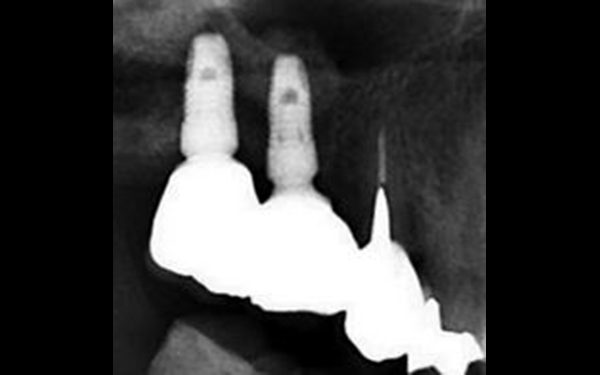

X光片顯示骨頭成功增高